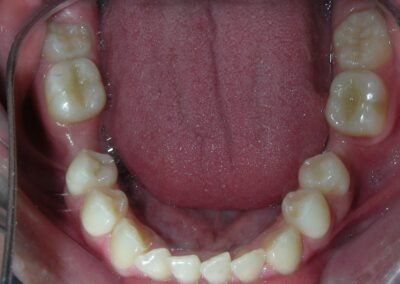

Simultaneously we begin with the alignment of the lower arch ,Simultaneously we began with the alignment of the lower arch with Roth prescription ceramic braces .022 . Henry Schein®

As the reader may infer, alignment and leveling of the upper anterior segment are being intentionally deferred at this stage of treatment. This strategic decision is based on the primary objective of closing the anterior open bite not through anterior extrusion, but by means of controlled posterior intrusion. This biomechanical approach promotes a counterclockwise rotation of the mandible, which leads to a increase in the facial axis angle and improvement in vertical facial proportions. By avoiding early anterior alignment, we prevent any premature vertical displacement of the upper incisors.